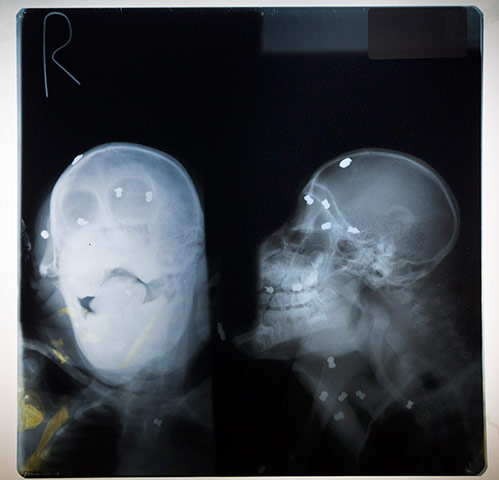

Οι διασώστες τον βρήκαν πάλι σε άθλια κατάσταση με ένα κόψιμο 40 εκατοστών στο αριστερό πόδι του και 62 σφαίρες από αεροβόλο όπλο στο σώμα και τα μάτια του.

Έπειτα από μεγάλη προσπάθεια κατάφεραν να αφαιρέσουν τις 14 από τις 62 σφαίρες. Το άτυχο ζώο τυφλώθηκε και πλέον ζει σε αιχμαλωσία.